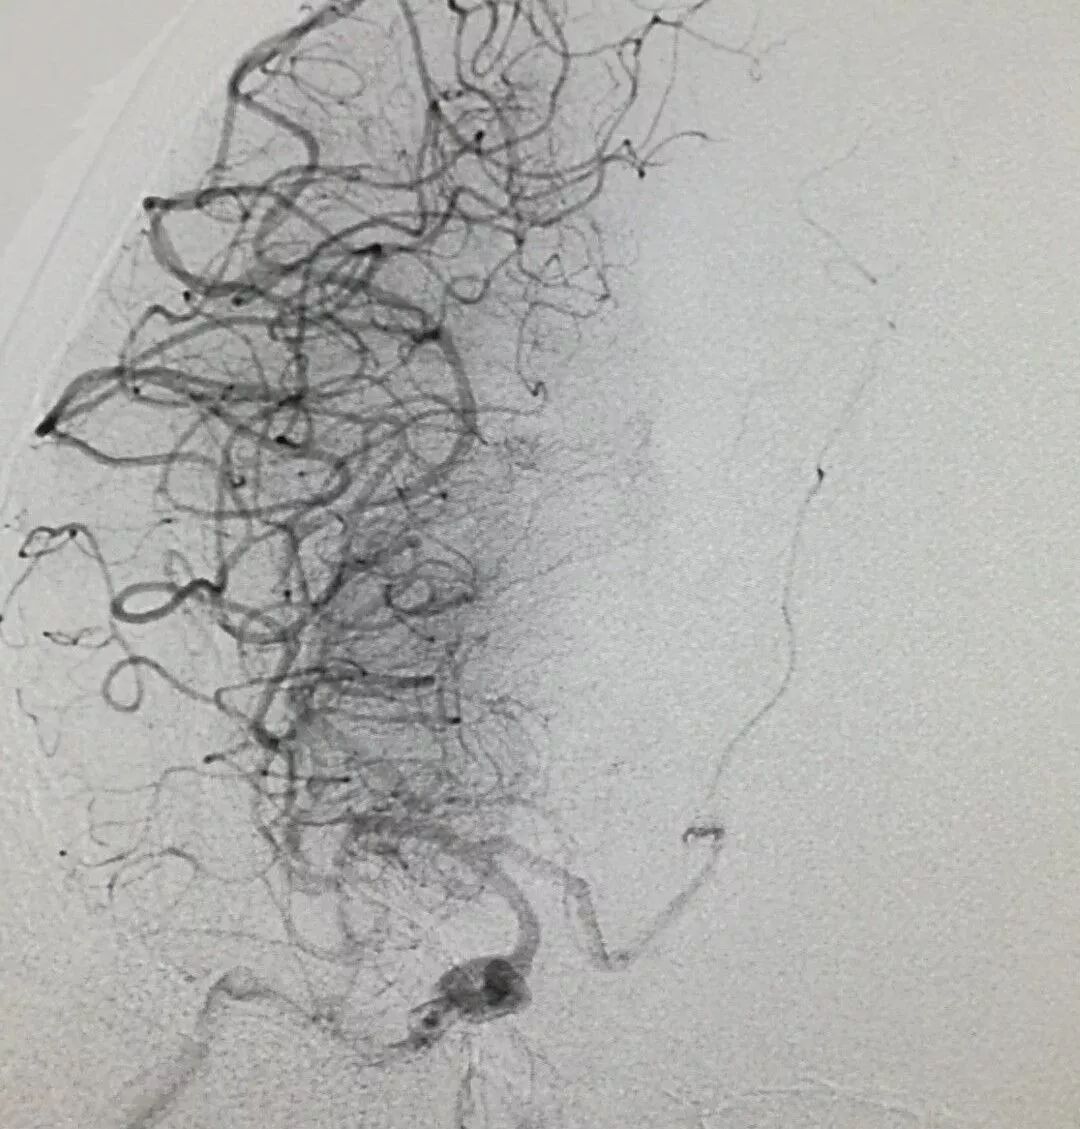

機(jī)械取栓,疏通生命要道——一小時成功搶救急性卒中患者!